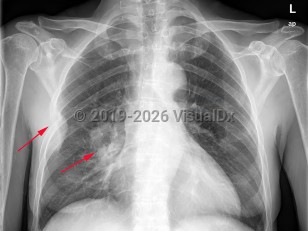

Chest pain, Dyspnea, 50-59 year old Female

Tension pneumothorax

Hemothorax